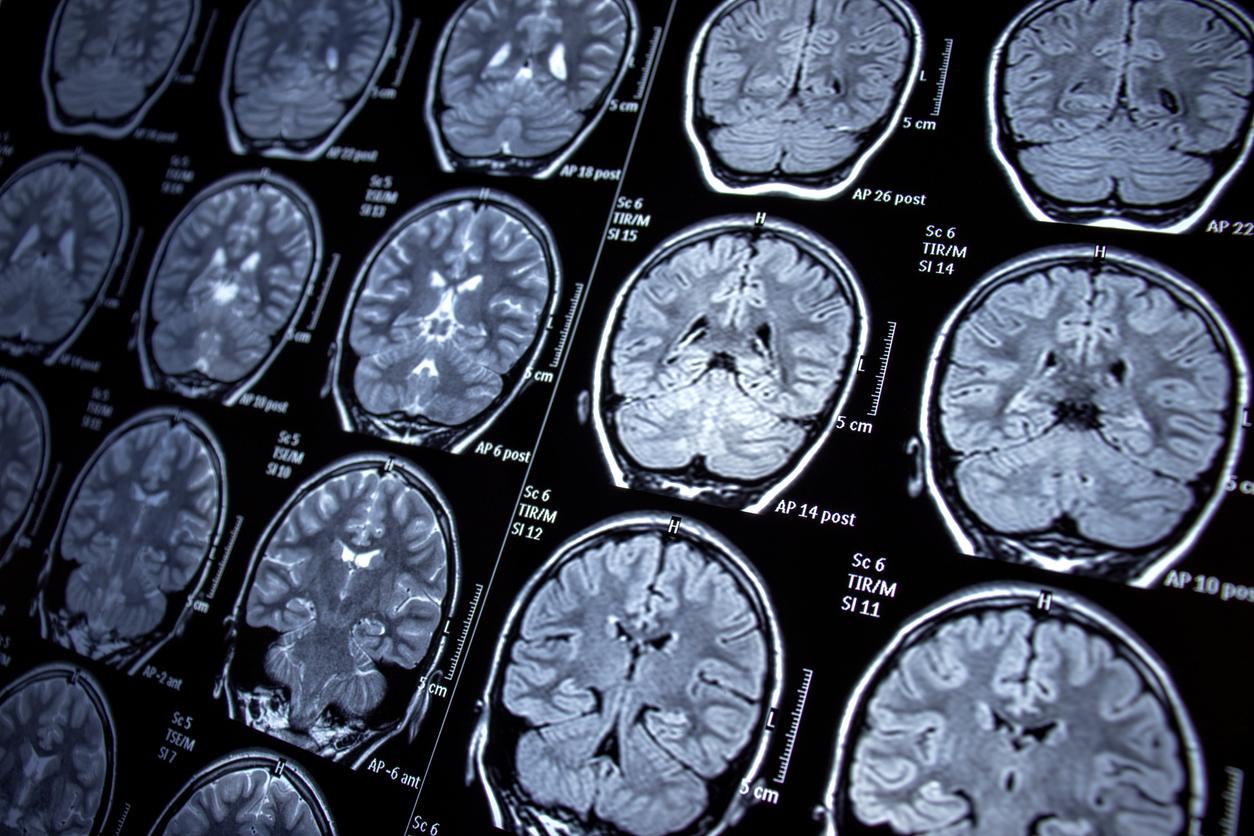

- Les crises d'épilepsie sont liées à des décharges électriques excessives dans certaines cellules cérébrales.

Selon l’Organisation mondiale de la santé, environ 50 millions de personnes sont atteintes d’épilepsie dans le monde. C’est "l’une des affections neurologiques les plus fréquentes", caractérisée par des crises de tremblements qui peuvent toucher tout ou une partie du corps. "Elles s’accompagnent parfois d’une perte de conscience et du contrôle de la vessie et de l’évacuation intestinale", précise l’OMS. La survenue d’une crise ne signifie par que la maladie deviendra chronique : jusqu’à 10 % de la population souffre d’au moins une crise d’épilepsie au cours de sa vie.